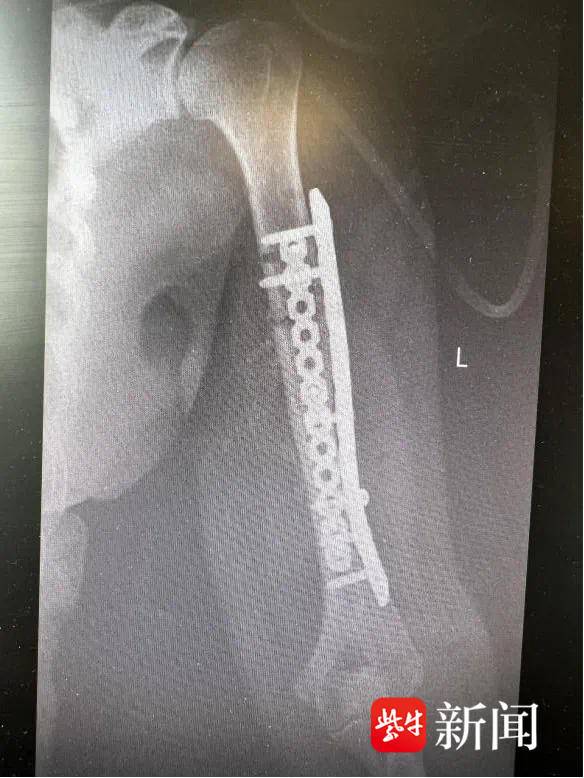

因此,等她的全身状况和伤口条件改善后,医疗团队按原定计划实施了第二阶段的功能修复手术。这次手术中,医生精细调整骨折对位,用更符合长期康复需求的内固定方式(钢板和螺钉)替代临时外固定支架,并对骨缺损部位进行植骨加固。同时,对膝关节的韧带损伤进行了针对性修复。

术后方阿姨手臂被重新接上

术后 方阿姨手臂被重新接上